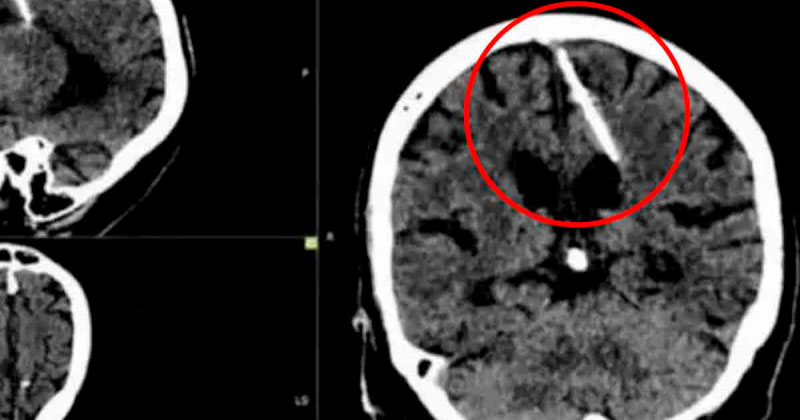

Abuelita se entera que tuvo una aguja en el cerebro por 80 años

Médicos detallaron que el objeto estuvo alojado en su cerebro desde su nacimiento y explicaron que es probable que sus padres hayan trataron de matarla en su infancia